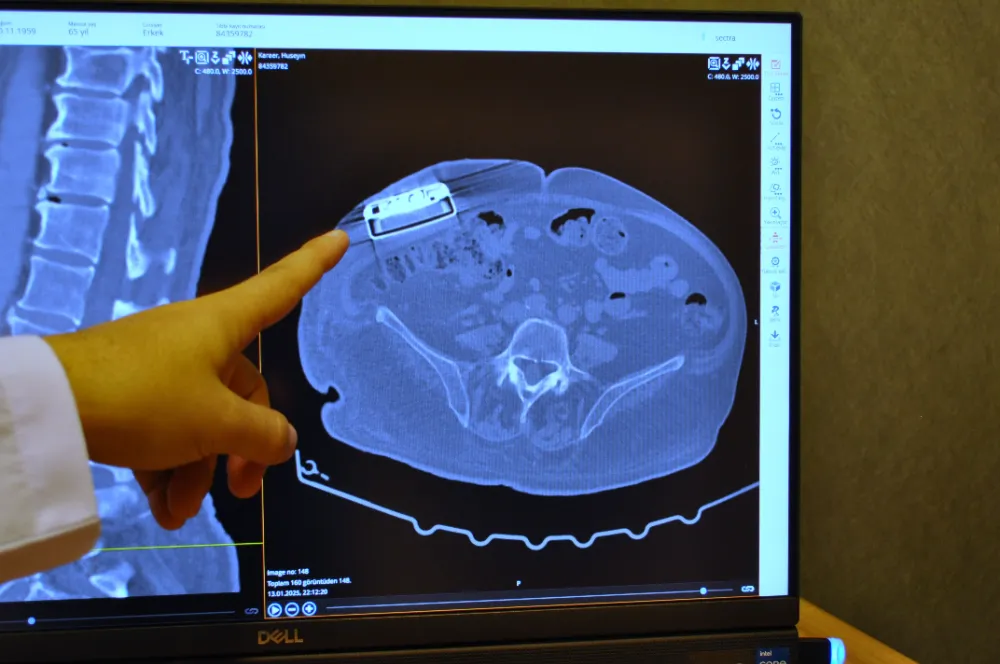

Operasyonla ilgili açıklamalarda bulunan Beyin ve Sinir Cerrahı Dr. Beşir Sürme, "65 yaşında erkek hasta, trafik kazasına bağlı bir omurilik hasarı geçiriyor ve bunun akabinde parapleji dediğimiz güç kaybı meydana geliyor. Gelişen bu omurilik hasarına bağlı hastada spastisite dediğimiz şiddetli kasılmalar oluşuyor ve hastaya baklofen pompası denilen bir cihaz implante ediliyor. Yaklaşık 11 sene önce implante edilen bu pompanın miadının dolması üzerine bize başvurdu ve biz bu hastamızda bir pompa değişimi ameliyatı gerçekleştirdik. Baklofen pompası tedavisi Türkiye'de daha önce de yapılan bir tedavi ancak biz yeni versiyon bir pompa yerleştirdik ve yeni özellikleri nedeniyle hastaya sağladığı özellikleri de gözlemledik" dedi.

Pompa tedavisinin daha önce uygulandığını ancak yeni teknoloji pompayı ilk kez erkek hastada kullandıklarını söyleyen Dr. Sürme, "Hastamızı yaklaşık 2 ay önce ameliyat ettik. Ameliyat sonrası programlamalarını yaptık. Bu hastalarda, hastalığın durumu ve hastanın ihtiyaçlarına göre verilecek ilacı pompa sayesinde programlayabiliyoruz. Programlamalardan sonra hastamız daha iyi olduğunu ve kasılmalarında belirgin düzelmeler olduğunu söylüyor. Hatta daha önceki pompaya göre şu an daha düşük doz ilaç vermemize rağmen hasta yine bundan fayda görebiliyor" şeklinde konuştu.